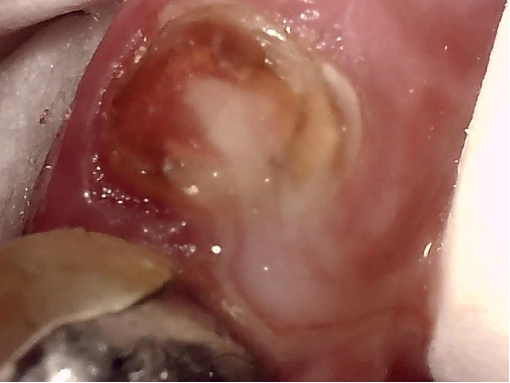

針が根管の先から嚢胞の中に出ています。本当は根管を拡大して取り出すほうがいいのですが、余りそれにこだわると根管を削り過ぎて歯が弱くなります。

今回は、嚢胞摘出術を行うのでその時に除去するので全く問題はありません。根管が開通したので嚢胞の中の膿が根管を通してどっと出て来ました。クリーム色の膿が流れ出ています。